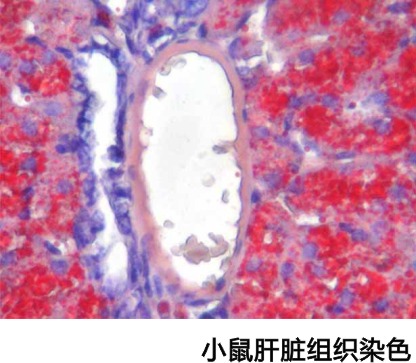

【產品介紹】正常情況下,除脂肪細胞外其他細胞內一般不見或僅見少量脂滴。在病理狀態下如這些細胞中出現脂滴或脂滴明顯增多,用脂肪染色能將脂質清晰地顯示出來。

【染色結果】脂肪被染成鮮紅色,細胞核染成深藍色,其他組織被染成淡藍色。

正常情況下,除脂肪細胞外其他細胞內一般不見或僅見少量脂滴。在病理狀態下如這些細胞中出現脂滴或脂滴明顯增多,用脂肪染色能將脂質清晰地顯示出來。